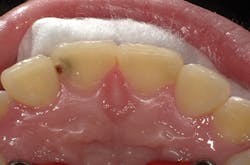

Figure 1

I'll demonstrate this material's versatility with a few cases. First is a large Class III cavity. The patient was extremely apprehensive, so we decided to prepare the cavity using the Lite Touch (AMD Lasers) erbium YAG laser. Very often, as in this case and the next few cases that we will depict, cavity preparation can be performed without anesthetic. In Figure 1, we see the preoperative image of the large Class III cavity on tooth No. 8. Using the Lite Touch laser (figure 2), we were able to excavate the entire cavity in a clean and efficient manner (figure 3). Using a fine diamond, a slight bevel was completed on the enamel at the cavo surface margin. By beveling the enamel, we improve the bond of the adhesive and allow for a seamless blend of the restorative material to the outer tooth structure. In deep restorations such as this, a calcium liner can help minimize sensitivity and act as a buffer between the restoration and pulp. Both Calcimol LC (Voco) and Theracal (Bisco) can be used in this manner. In this case, we decided to use Theracal. Theracal was placed in the deepest area and light-cured for 15 seconds (figure 4). After a 37% phosphoric acid etch of the enamel margin, we applied Futurabond U (Voco) as per the manufacturer's instructions and light-cured for 10 seconds. Admira Fusion shade A2 was placed in three increments and polished. The final restoration exhibits a beautiful luster and a seamless blend from the restoration to the natural tooth (figure 5).